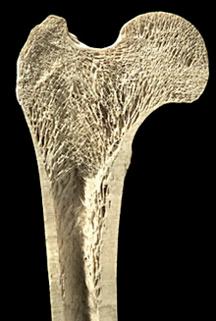

Die exakte Analyse der Beingeometrie basiert auf Ganzbein-Röntgenaufnahmen und ggf. Computertomographie. Auf der Basis dieser bildgebenden Diagnostik werden mit dem Patienten die verschiedenen Therapieoptionen besprochen und die Operation geplant. Aufgrund von blutsparenden minimal invasiven Operationstechniken muss nicht mit Bluttransfusionen gerechnet werden. Die Operation findet in Vollnarkose statt und dauert bei

simultaner Anwendung mehrere Stunden. Der Nagel wird nach Vorbereiten der Markhöhle durch einen einzigen kleinen Schnitt eingebracht. Lange Röhrenknochen besitzen eine feste äußere kompakte Knochenschicht. Im Inneren bestehen sie in Gelenknähe aus Knochenbälkchen, im Schaftbereich befindet sich innen die Markhöhle für das Knochenmark. Diese Knochenbälkchen ermöglichen eine stabile Leichtbauweise.

In diese Markhöhle wird der Nagel nach Aufbohren eingebracht.